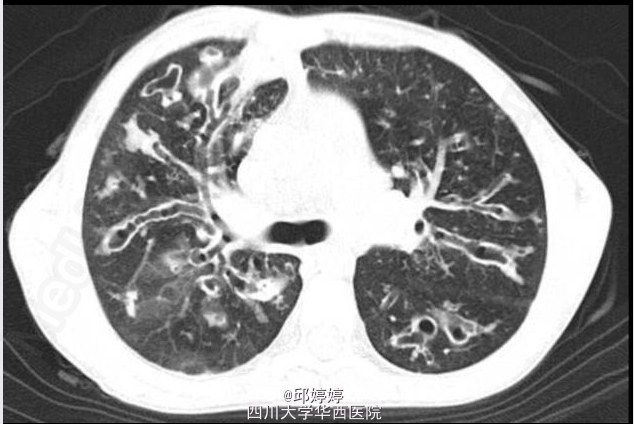

查体:呼吸急促,双肺呼吸音粗,可闻及干、湿啰音。胸部CT如图。

诊断:囊性纤维化。痰培养:绿脓杆菌,是囊性纤维化感染并发症中最常见的致病菌。